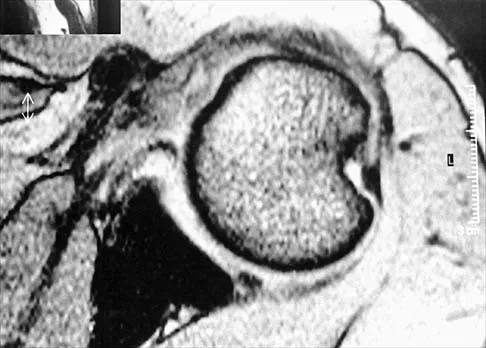

Figure 47 shows a transverse MRI scan of a patient's left shoulder. The findings reveal which of the following abnormalities?

Explanation

The MRI scan shows a defect in the posterior aspect of the humeral head, commonly referred to as a Hill-Sachs lesion. This is an impaction fracture of the humeral head that occurs during anterior shoulder dislocation. The abnormality on this image is an irregularity of the posterior humeral head; the humeral head otherwise has a homogenous appearance. The coracoid, subscapularis, and posterior labrum are normal. Griffin LY (ed): Orthopaedic Knowledge Update: Sports Medicine. Rosemont, IL, American Academy of Orthopaedic Surgeons, 1994, pp 47-63.